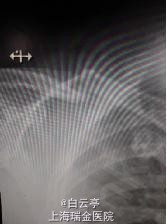

查体:右侧锁骨突起, 疼痛拒按。 右上肢远端血运感觉正常。右上臂活动受限。 辅助检查:x片提示患者右侧锁骨骨折。

诊断:右侧锁骨中段骨折。 治疗:切开复位内固定术。